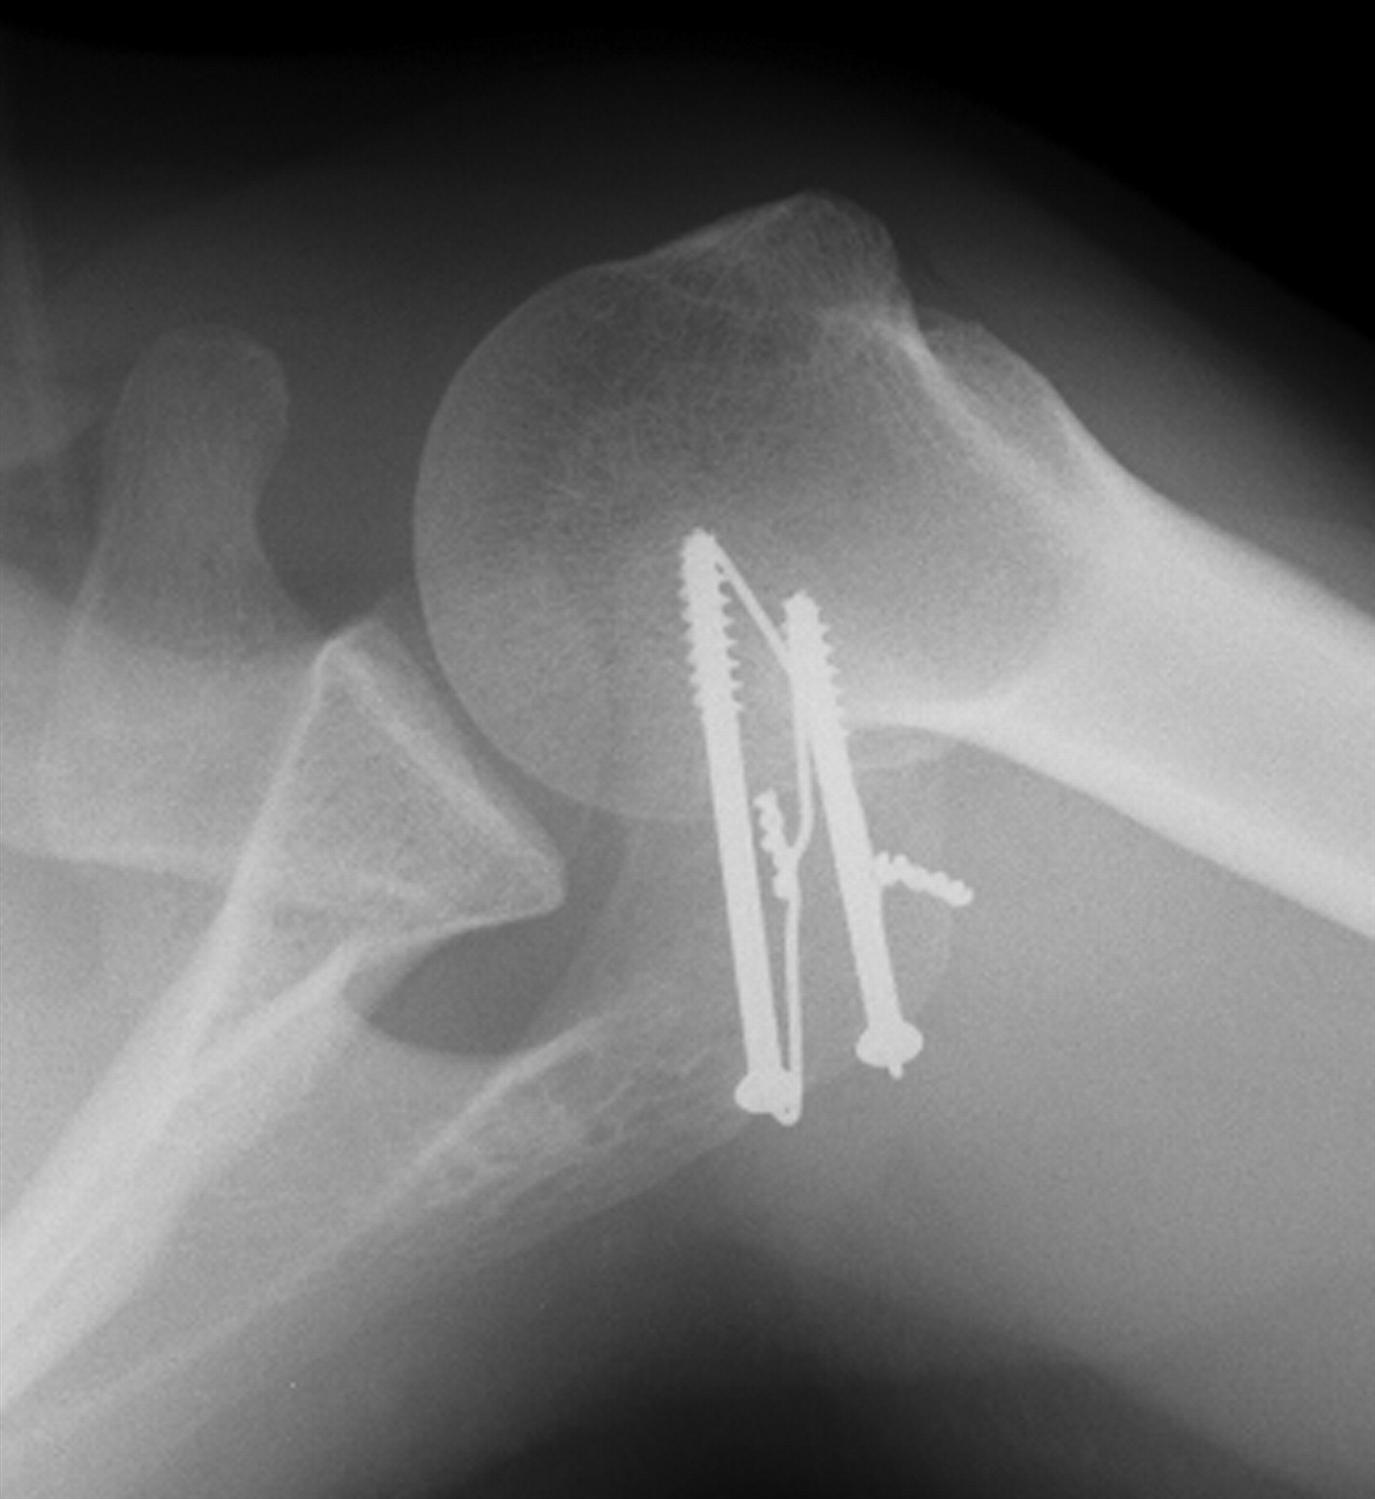

Shoulder fusion after a selfinflicted gunshot wound Bone & Joint Fused Shoulder Blade People with fshd have weakness in the muscles that help raise their arms and they may have winging of the scapula (shoulder blades). The three bones that meet at the shoulder joint include the bone in the arm (humerus), the shoulder blade (scapula), and. Nerve damage or massive rotator cuff tears may. Thoracoscapular fusion is indicated for loss of power.. Fused Shoulder Blade.

Xray of my fused left shoulder r/medizzy Fused Shoulder Blade Thoracoscapular fusion is indicated for loss of power. People with fshd have weakness in the muscles that help raise their arms and they may have winging of the scapula (shoulder blades). The most common use of shoulder fusion is after severe shoulder injury from car accidents. Nerve damage or massive rotator cuff tears may. Os acromiale is a condition in. Fused Shoulder Blade.